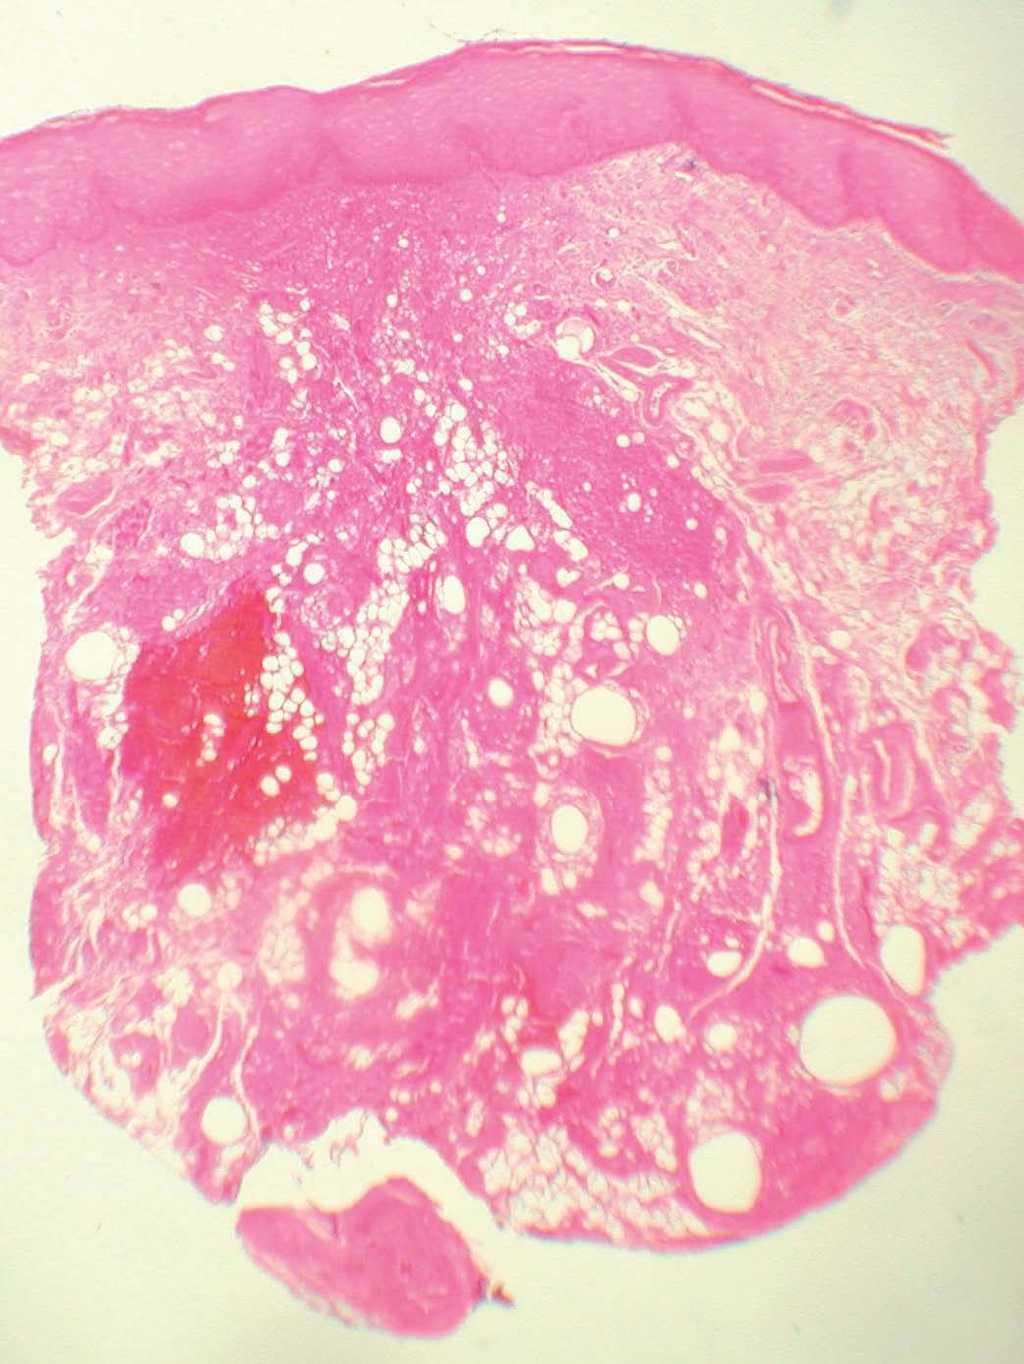

Se le realizó una biopsia en sacabocados de 6 mm de la lesión. La tinción con hematoxilina-eosina fue diagnóstica (figs. 2 y 3).

Fig. 3.--Vacuolas de tamaño y forma variables. (Hematoxilina-eosina, x100.)

Se observaba un denso infiltrado inflamatorio que se extendía desde la dermis media hasta al tejido celular subcutáneo, rodeando estructuras vacuolazas claras, variables tanto en la forma como en el tamaño y con apariencia espumosa. El infiltrado inflamatorio estaba formado por células epiteloides, histiocitos, linfocitos y células gigantes multinucleadas (figs. 2 y 3).

Histológicamente la silicona puede encontrarse tanto en el espacio intracelular como extracelular. En este último caso muestra una apariencia espumosa, con muchas vacuolas claras, sin birrefringencia y con formas y tamaños variables. Se encuentran rodeadas por un infiltrado granulomatoso compuesto por histiocitos, linfocitos y células gigantes multinucleadas. Estos nódulos granulomatosos se extienden desde la dermis al tejido celular subcutáneo y están rodeados por bandas de tejido conjuntivo 3. Con frecuencia pueden apreciarse cuerpos asteroides, angulados, translúcidos y birrefringentes en el interior del citoplasma de las células gigantes multinucleadas, que corresponden a impurezas de la silicona. Artecoll® es uno de los mejores materiales de relleno permanente empleados actualmente para la corrección de arrugas y el aumento de labios, debido a sus resultados cosméticos prolongados y a la escasa frecuencia de efectos adversos. Consiste en una suspensión compuesta por el 25 % de microesferas de polimetilmetacrilato (PMMA) de 30 a 40 micras de diámetro y el 75 % de una solución al 3,5 % de colágeno. Sólo el 3 % de casos sufren complicaciones, el 0,1 % de las cuales corresponden a granulomas. Típicamente, los granulomas por Artecoll® aparecen de 6 a 24 meses tras la infiltración. Se puede evitar esta reacción teniendo en cuenta que debe infiltrarse profundamente, entre la dermis y el tejido celular subcutáneo. Los granulomas se producen cuando la inyección es demasiado superficial o cuando se realizan retoques 1-7. En la histología se aprecia un infiltrado granulomatoso dérmico difuso formado por vacuolas redondeadas extracelulares, sin birrefringencia, de tamaño y forma uniforme rodeadas de histiocitos y células gigantes multinucleadas 3.